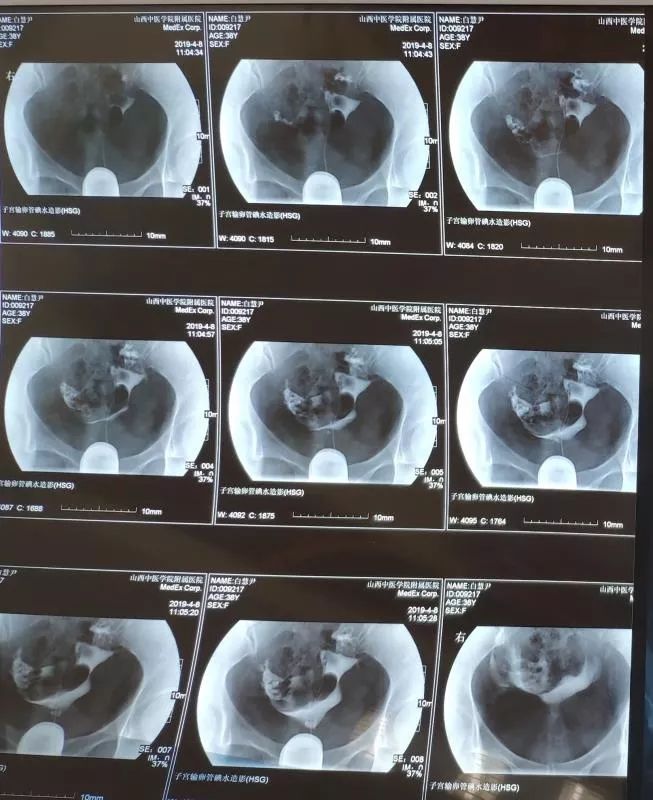

在不孕不育科中药内服+外治(中药保留灌肠+热敷)治疗三个月后,复查子宫输卵管造影:双侧输卵管通而不畅,造影剂弥散均匀,该患者经治疗后输卵管由不通转为通畅。